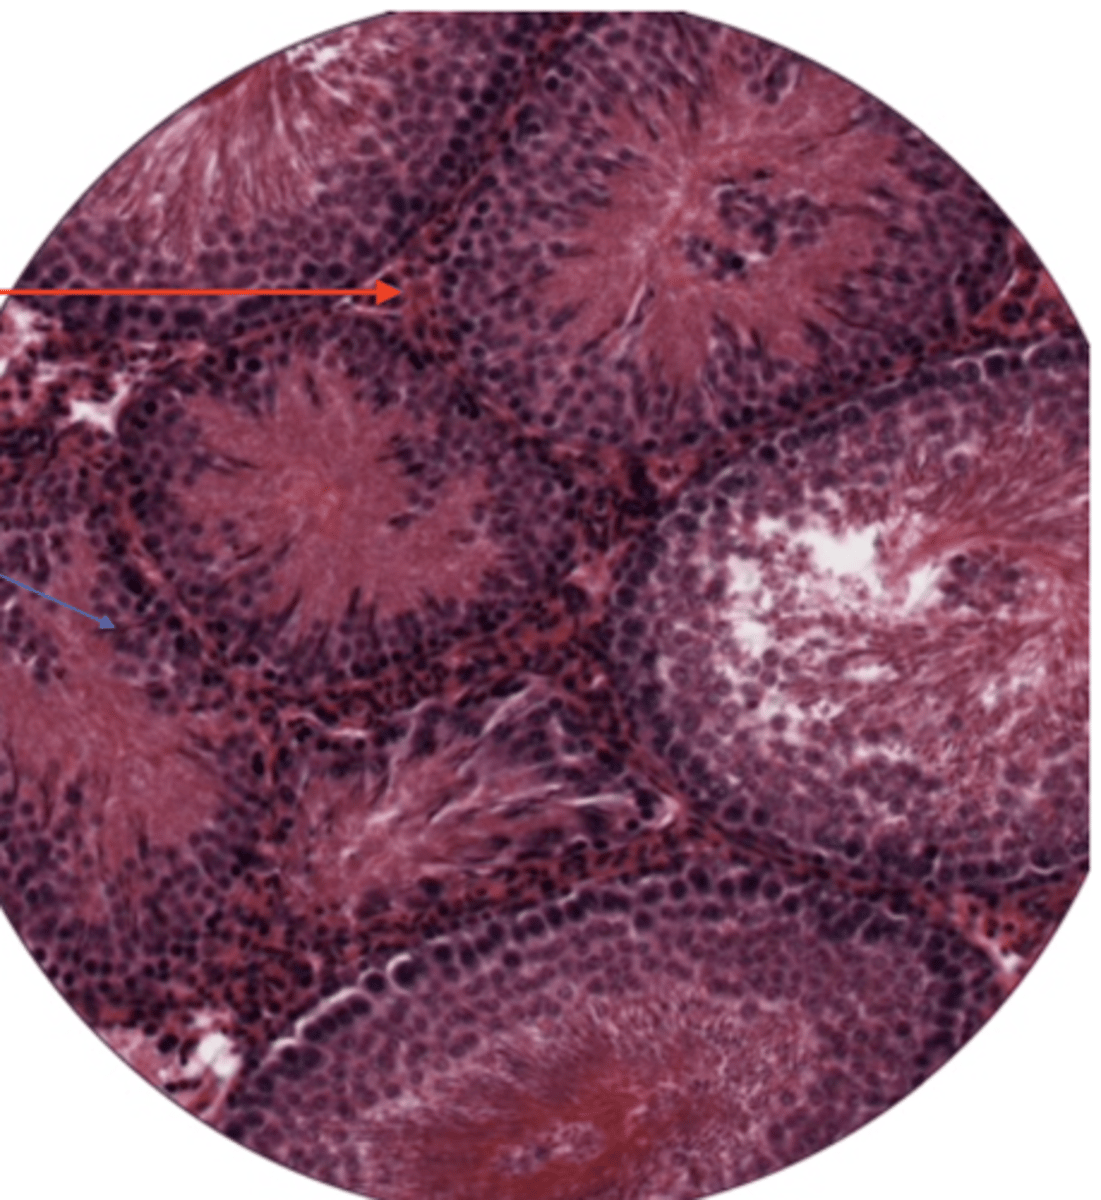

seminiferous tubule

leydig cells

sperm cell

sperm mass